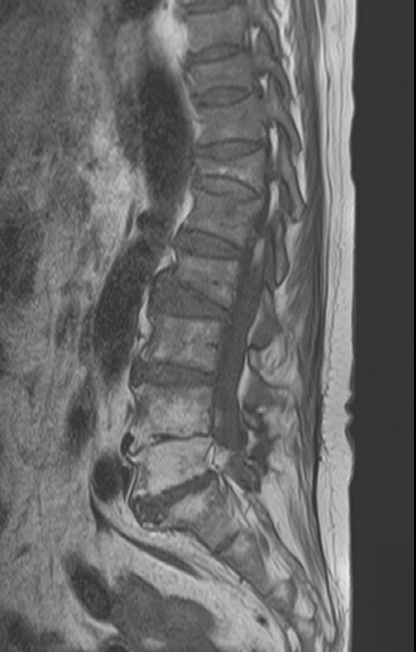

-L Spine MRI

-심한 과호흡 상태에서 검사 시행

-검사 도중 계속 움직임

-Motion Artipact 심하여 scan time 짧게 조정함.

- flattening of T10 through L2 bodies with partially fatty bone marrow and some sclerotic change

- herniation of discs T10-11 through T12-L1 discs into adjacent vertebral bodies

1. old T10 through L2 compression fracture with schmorl's nodes

2. L2-3, L3-4 and L5-S1 diffuse bulging discs

3. mild L2-3 and L3-4 central stenosis

4. moderate stenosis of left L5-S1 neural foramen

5. degenerative spondylosis